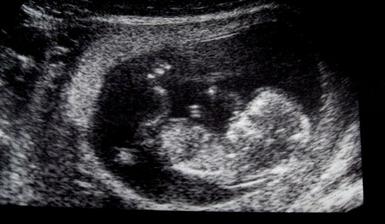

23.5. - 3D ultrazvuk - naozaj zážitok, už vieme, že čakáme druhého chlapčeka. Má 350g a 20cm bez nožičiek 🙂

26.5. - UTZ Motol - všetko je tak, ako má byť 🙂 HURÁ!!